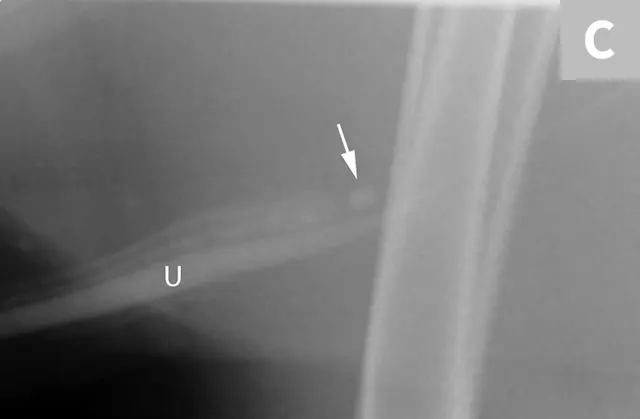

FIGURE 7A

Lateral abdominal radiograph of a cat with multiple, small, oval mineral opacities superimposed over the ventral aspect of the retroperitoneal space (arrows). These mineral opacities are arranged linearly extending from the caudal aspect of the kidneys to the level of the urinary bladder.

Differentiation between a complete vs partial ureteral obstruction can be difficult with survey radiography and ultrasonography alone. Antegrade pyelography (nephropyelocentesis with renal pelvic injection of iodinated positive contrast medium using ultrasound guidance) may be useful for documenting a complete vs partial obstruction (Figure 7).11

Antegrade pyelography is beneficial when compared with standard IV urography, as it lowers the risk of potential contrast-induced renal damage and provides excellent filling of the renal collecting system, regardless of renal function.11